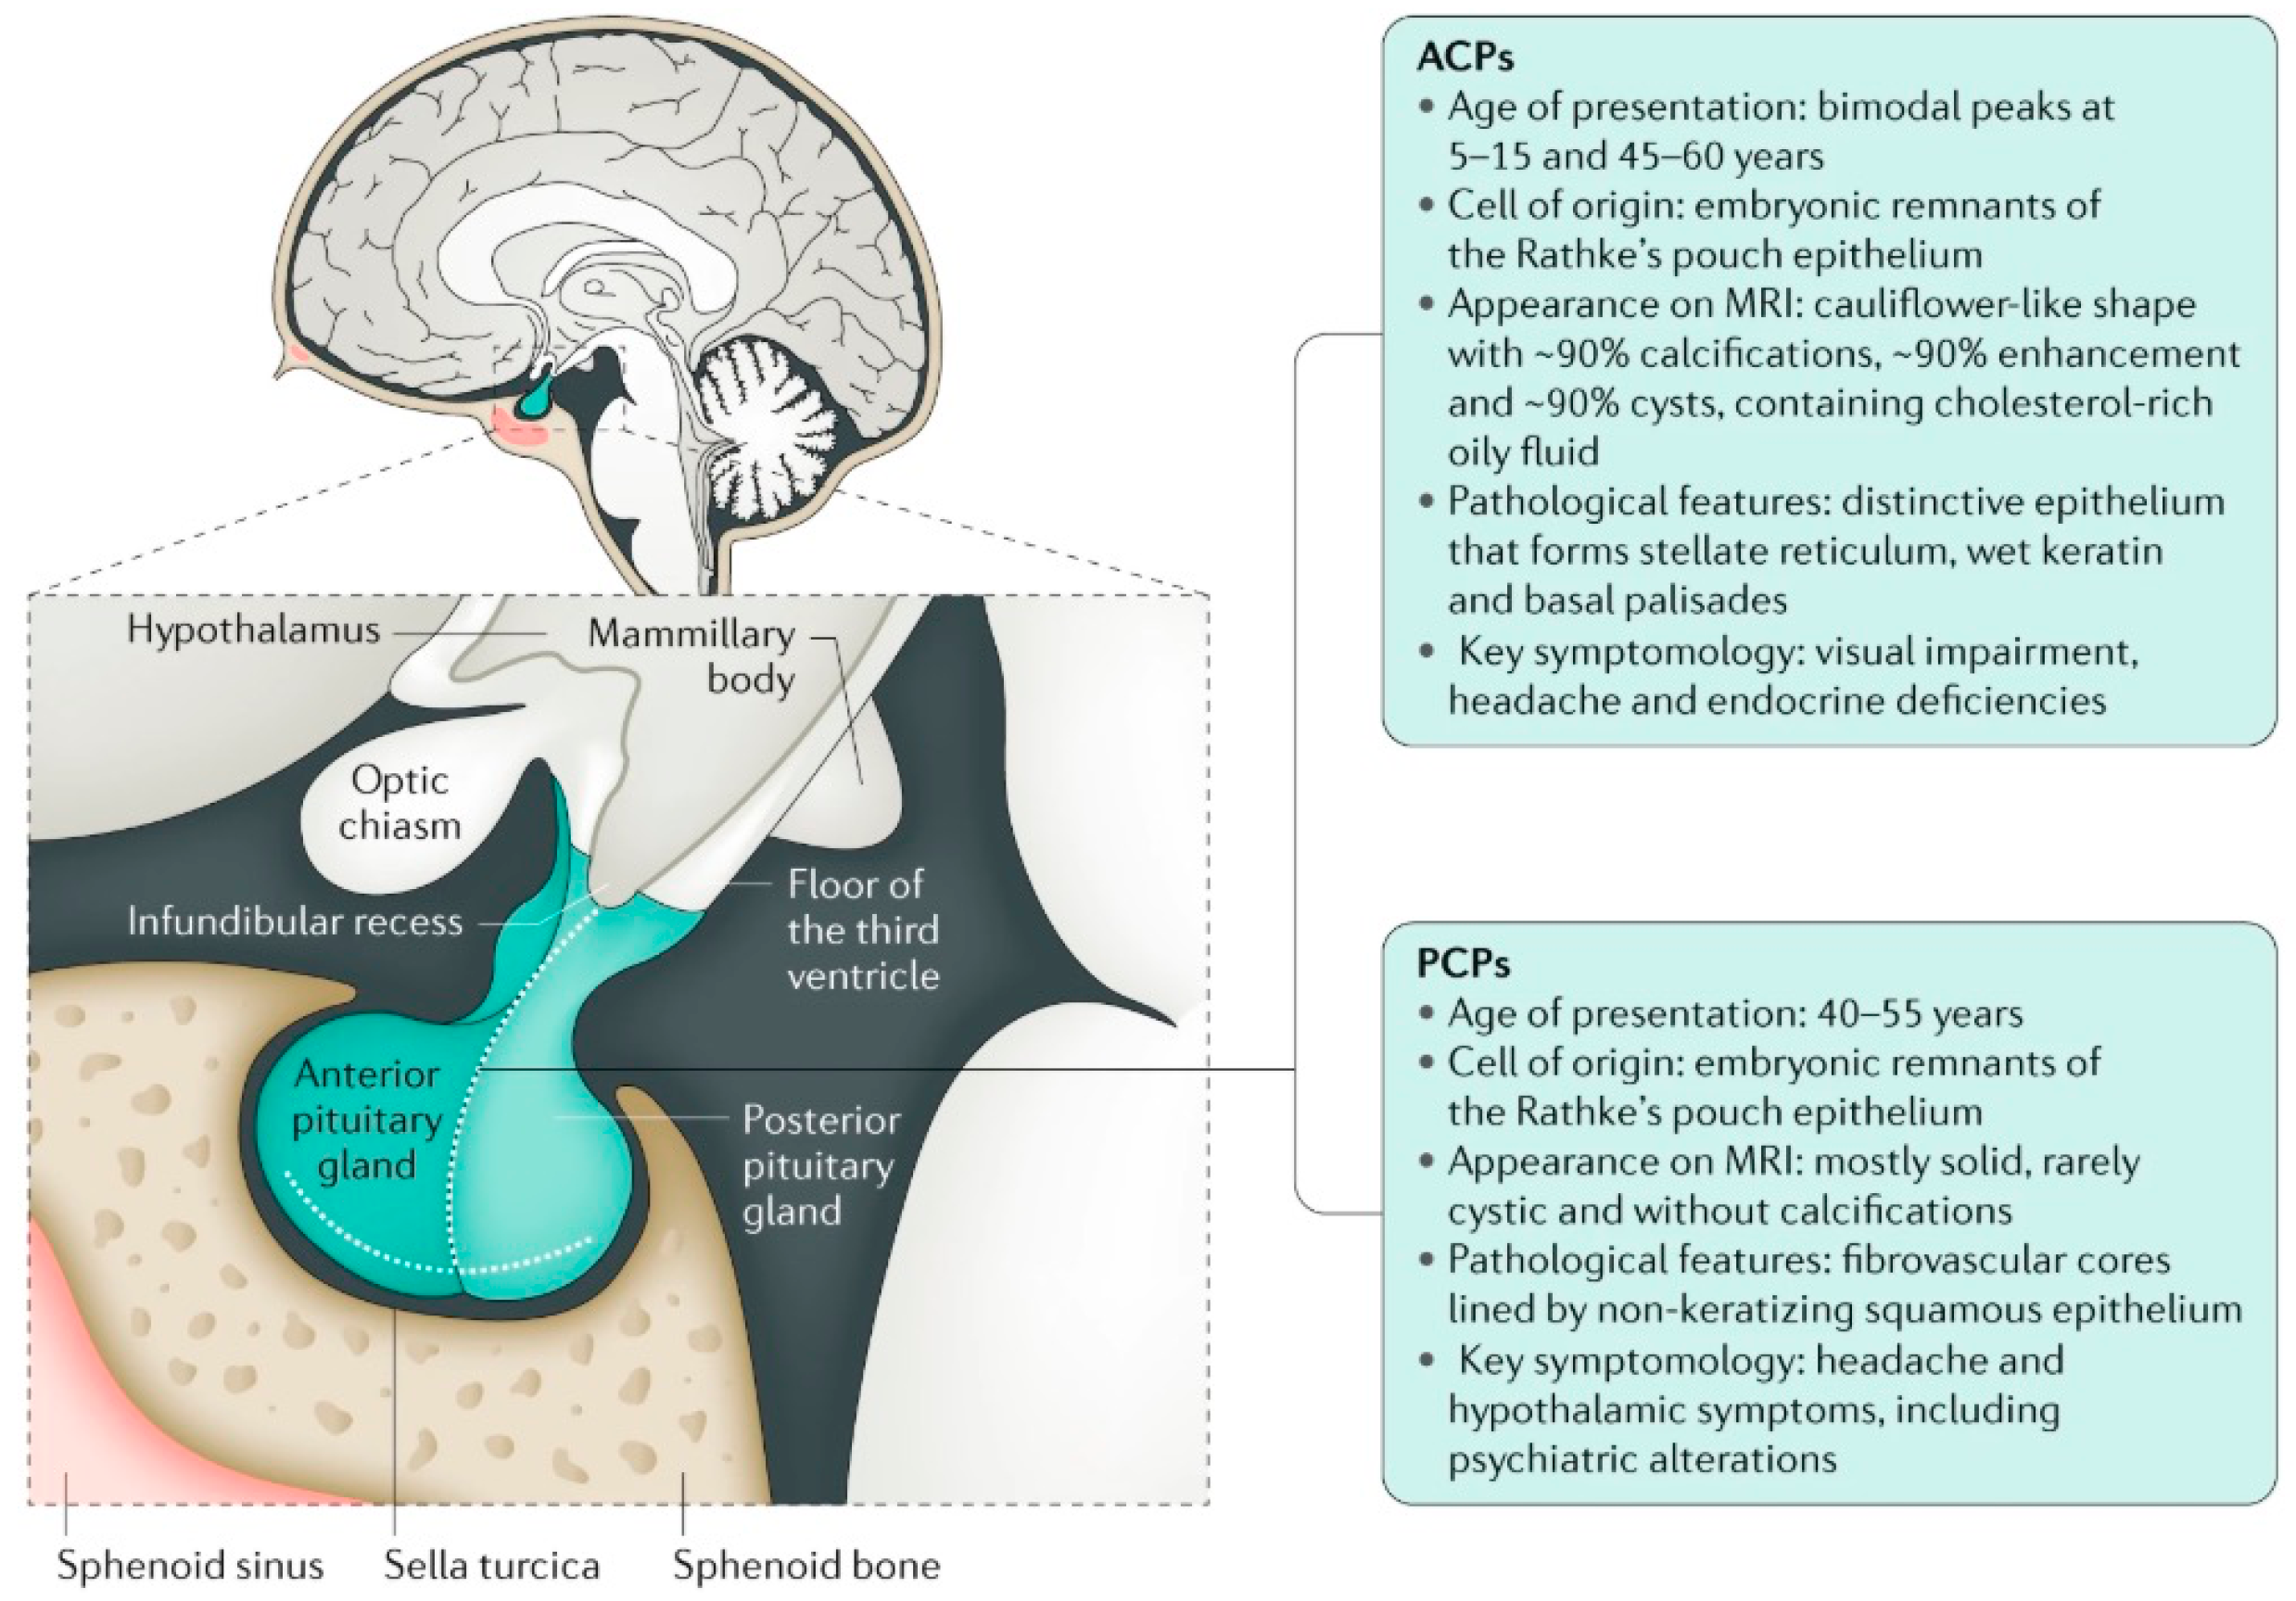

2. Anatomical Location of Childhood-Onset Craniopharyngioma Close to the Hypothalamus